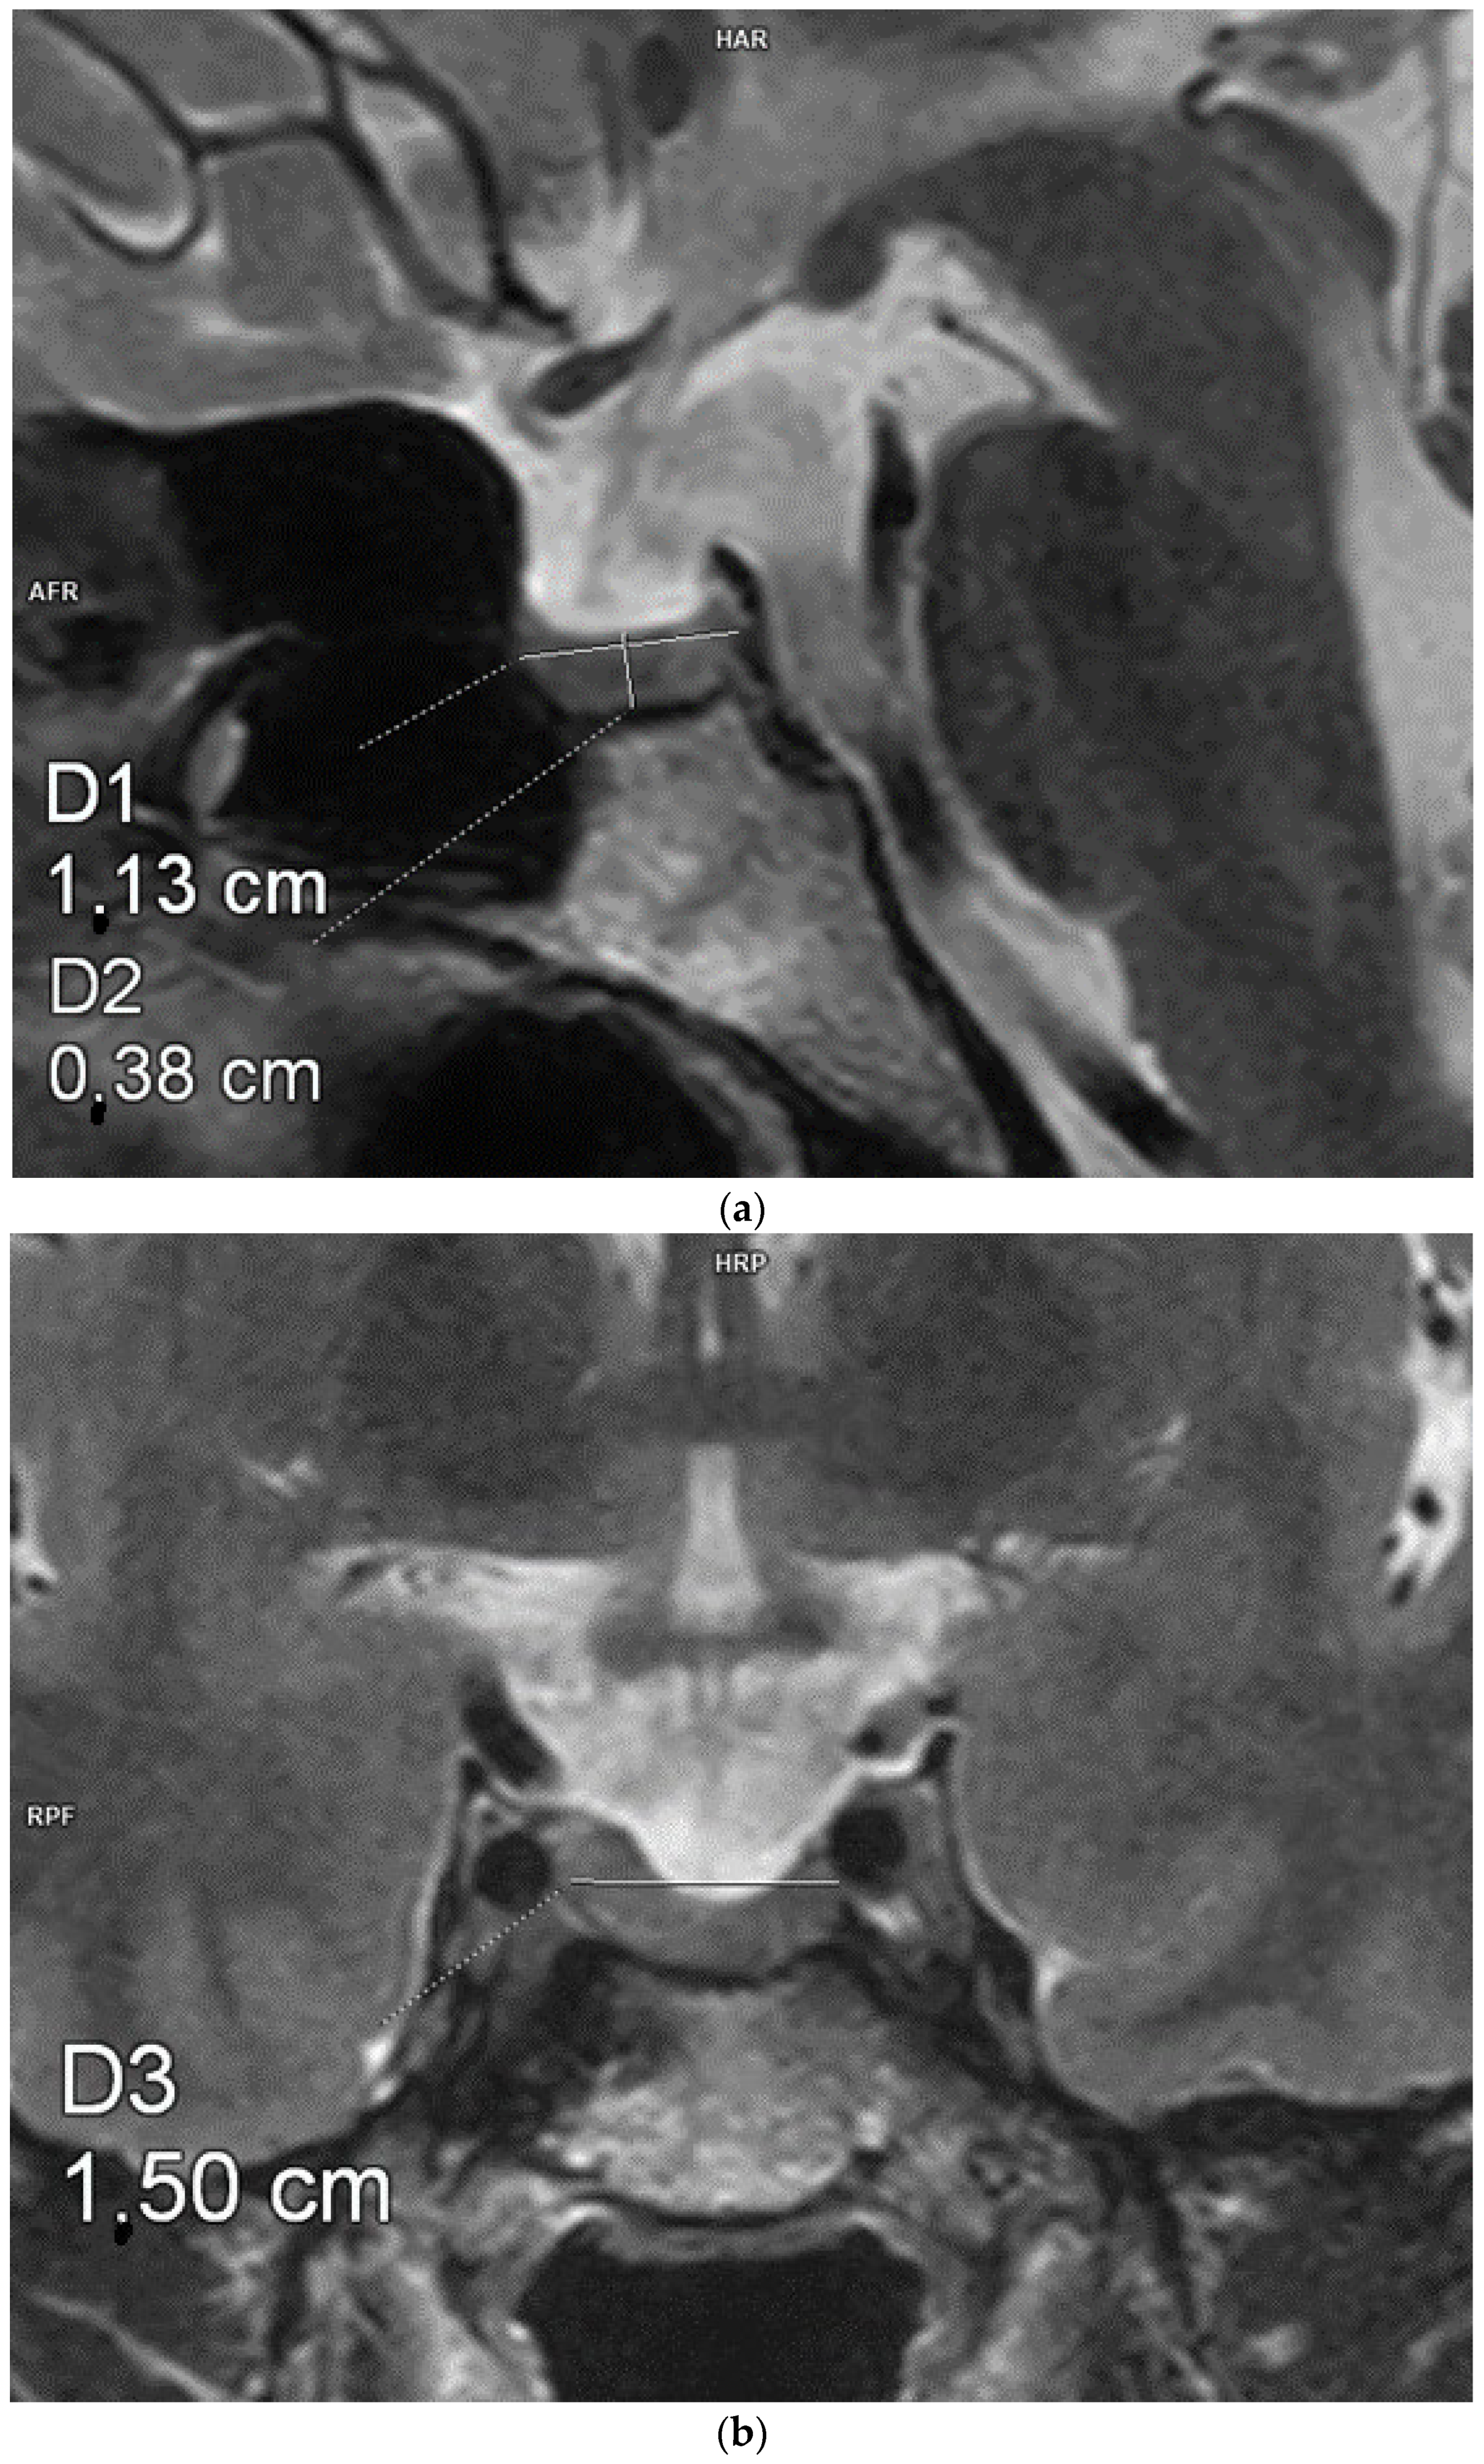

Each patient underwent an MRI of the pituitary gland at the Department of Radiological Diagnostics of the National Medical Institute of the Ministry of the Interior and Administration. The examination was performed according to the pituitary protocol, with T1- (+Dixon) and T2-weighted, FLAIR, T2 STIR, and T1-weighted images being recorded after contrast administration using a 3.0 Tesla scanner with a slice thickness of 2 mm, slice gap of 0, field of view 150/150, matrix 240/300, and pixel alimentation of 0.5 × 0.625 mm. The AP, CC, and transverse diameters of the pituitary were measured. The pituitary volume was calculated according to a simplified formula for a rotational ellipsoid (volume = 0.5 × AP diameter × transverse diameter × CC diameter). Figure 1, Figure 2 and Figure 3 show example measurements and calculations of the pituitary volume. The following parameters were also evaluated: pituitary concavity (i.e., its indented appearance) in the coronal and sagittal planes, preserved high signal of the posterior lobe of the pituitary gland in T1-weighted images, anteroposterior or lateral displacement of the pituitary stalk (i.e., infundibular deviation without disruption in its continuity), and suprasellar cistern herniation occupying the upper third or the upper two-thirds of the sella turcica.

Figure 3.

Measurements of the pituitary gland. Magnetic resonance imaging, T2-weighted images in the sagittal (a) and coronal (b) planes. The craniocaudal, transverse, and anterioposterior dimensions of the pituitary gland are 3.8 mm × 11.3 mm × 15 mm.